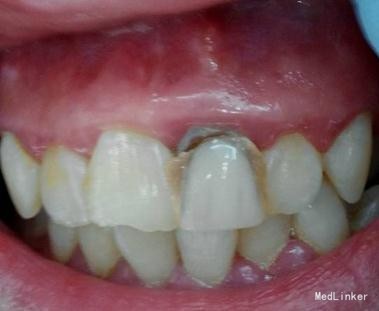

检查:21 自凝树脂桩核修复,树脂冠略有松动,叩诊无明显不适,唇侧牙龈有一陈旧性瘘管。

X-ray显示根管治疗不完善。

诊断:21不良修复体